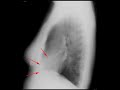

This is a 59 year old man who presents with shortness of breath. A routine chest radiograph was obtained. There is a curvilinear region of increased density consistent with calcification overlying the region of the left ventricle. On the lateral radiograph, the shape of the curvilinear calcification is better appreciated. Differential considerations would include pericardial calcification, less likely pleural calcification, or calcification of a left ventricular aneurysm. Given the findings on chest xray, the patient underwent an echocardiogram which demonstrated dyskinesia of the anterior wall and apex of the left ventricule. The conglomerate of findings is most consistent with a calcified left ventricular aneurysm in the setting of a previous myocardial infarction.